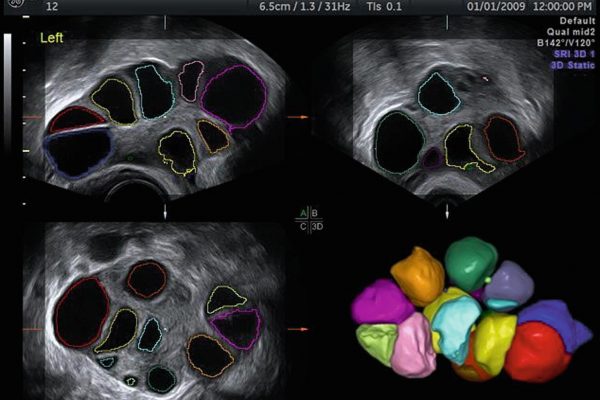

Optimalno je da to bude period između 7. i 10. dana ciklusa. Pretrage započinju uzimanjem uzoraka krvi zbog analiza polnih hormona i hormona štitne žlijezde. Nakon uzimanja uzorka krvi radi se 3D ultrazvučni pregled materične šupljine sa ciljem provjere građe materične šupljine, 3D pregled jajnika sa ciljem procjene “rezerve jajnika”, potom se provodi procedura testiranja prohodnosti jajovoda također pod kontrolom 3D ultrazvuka. Istovremeno mušarac daje uzorak sjemena za analizu (potrebno je 3.-5. dana apstinencije)

- 3D pregled građe materične šupljine

- 3D pirkaz jajnika sa ciljem procjene “rezerve” jajnika (AFC)

- 3D sono HSG (test prohodnosti jajovoda sa trodimenzonalnim prikazom)